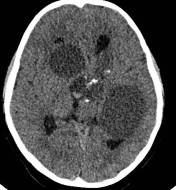

病例1:患儿男性,9岁。因反复出现意识丧失、视力下降半年收入院。入院后CT及 MRI显示颅内有形态不规则、“超大型”的颅咽管瘤,最大径约10厘米,见图1、图2。

图1.术前CT显示典型的囊性颅咽管瘤